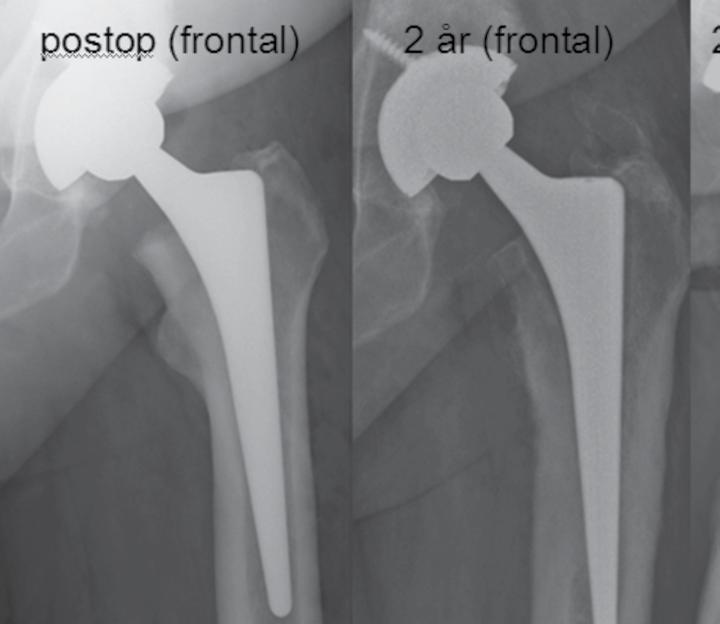

50 årig man som två år tidigare opererats

med en ocementerad protes. Han blev aldrig smärtfri efter operationen. Söker på grund av lårsmärtor som förvärras vid belastning. Daglig hög analgetikakonsumtion. CRP 7 (normalvärde <5). Använder 1 kryckkäpp.

a. Vilken diagnos bör du misstänka i första hand? (1p)

b. Motivera ditt svar och ange förslag till behandling. (2p)

a. Patienten har smärtor både i vila och vid belastning. CRP är antytt förhöjd. Protesen har en bred zon proximalt. Det föreligger en breddökad kortex och uttalade periostala pålagringar.

Mycket talar för en djup och lågvirulent infektion. (1 p). (Stammen är sannolikt lös även om man inte kan se någon säker sjunkning. Cupen sitter troligen fast eftersom man inte ser någon zon)

b. Man bör göra en ledpunktion och odla helst vid två efterföljande tillfällen (1p). Härefter protesbyte (1p). Om agens inte är känt bör revision utföras i två seanser.